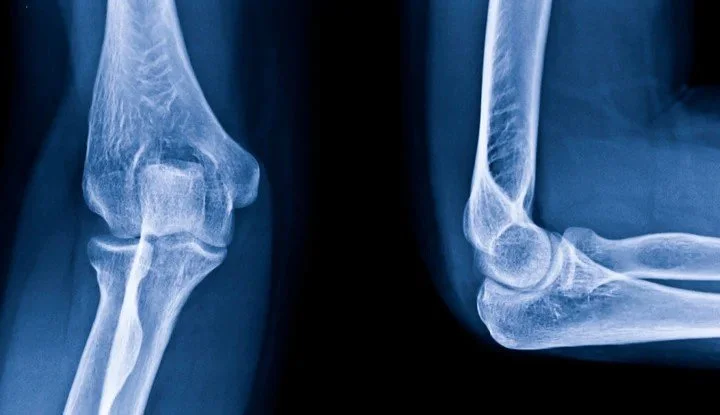

X-ray: Often, the first type of imaging used is a plain X-ray. An X-ray will convey important information with respect to bone and joint issues, particularly osteoarthritis, and assess for unexpected more serious pathologies, such as a cancer. Stress or weight-bearing views may also provide important information in joint instability, such as in a Lis Franc injury in the foot. It is also the cheapest type of imaging, with many sequences significantly covered by Medicare. However, if purely assessing soft tissue structures, such as muscle or ligament, there are more suitable imaging modalities that should be used instead.